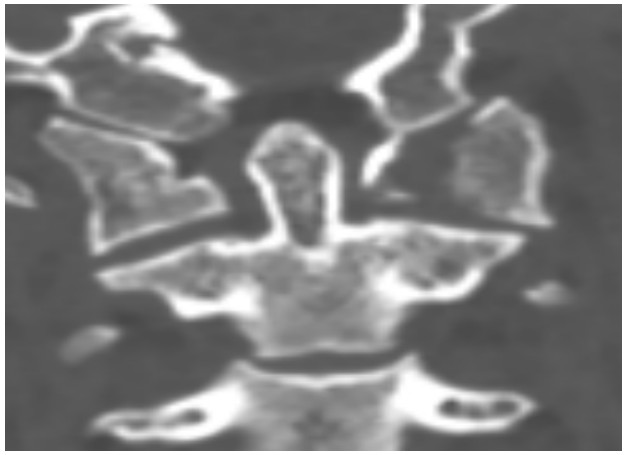

國慶節(jié)前一天,譚女士不幸被門框砸傷頸部,劇烈的疼痛和頸椎的活動受限讓她的世界瞬間陷入了黑暗。在經(jīng)歷了初步的檢查后,譚女士被診斷為寰椎骨折,這個診斷如同一道晴天霹靂,讓她和家人的心沉入了谷底。絕望中,譚女士被緊急轉(zhuǎn)至衡陽市中心醫(yī)院骨科一區(qū)(脊柱外科),錢軍博士及其團隊在接到這一緊急病例后迅速接診,經(jīng)過細致的病史詢問、體格檢查和影像學(xué)資料分析,確診譚女士的寰椎骨折伴有寰樞椎體不穩(wěn)定,迫切需要手術(shù)治療以恢復(fù)其穩(wěn)定性??紤]到上頸椎手術(shù)的高風(fēng)險性,特別是寰樞椎周圍結(jié)構(gòu)復(fù)雜,緊鄰椎動脈和脊髓,手術(shù)過程中的任何微小失誤都可能導(dǎo)致災(zāi)難性后果,錢軍博士團隊頂著壓力,迎難而上,沒有絲毫猶豫,立即行急診手術(shù),投入到緊張的救治工作中。